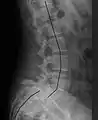

Degenerative spondylolisthesis at L5 - S1.

(A) CT sagittal view of a low grade slip.

(B) Lateral radiograph pre-operative intervention.

(C) Surgically treated with L5 – S1 decompression, instrumented fusion and placement of an interbody graft between L5 and S1.

Both minimally invasive and open surgical techniques are used to treat anterolisthesis.[43]